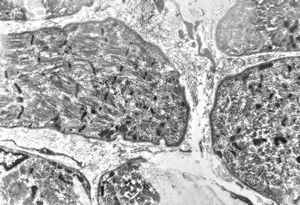

F,25y. | myopathy - atrophic and regenerating muscle cells